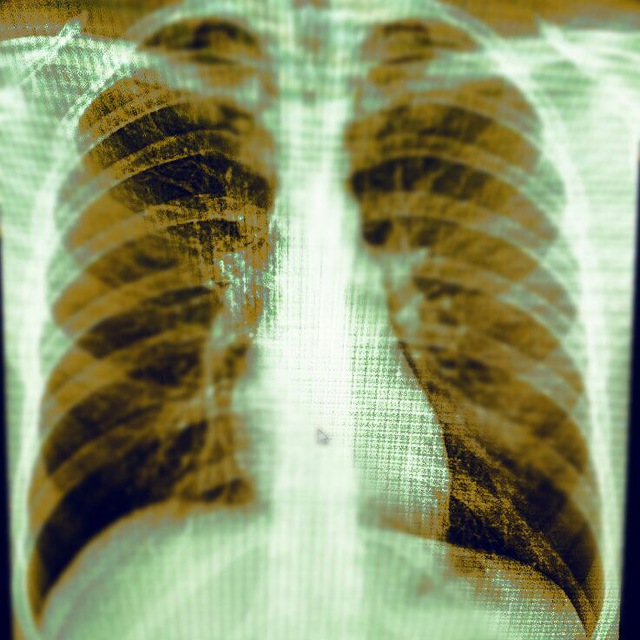

Добрый вечер, коллеги. М, 60 лет. А анамнезе рак правого лёгкого с мтс. Сейчас темп 37.2, кашель с мокротой. Пришли исключить пневмонию.

По-моему нету пневмонии, вы как считаете?

Справа в нижней доле - участок инфильтрации, гидроторакс

S6,S4-5,возмоно выпот ,МСКТ

И все таки пришёл ковид сегодня

Правосторонная плевро пневмония